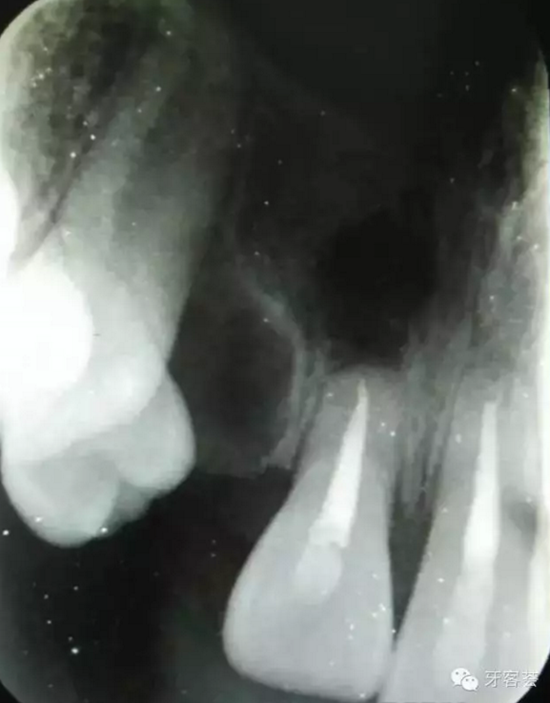

圖2:術(shù)前的全景片檢查:12牙根畸形。11、21根尖1/3橫折??上Э床磺甯鈾M折。

圖3:根尖片可以清晰看到11、21根尖橫折,這是根管治療過(guò)程中的試尖。

圖4:根充完成后,11根尖橫折。21根尖橫折部分已經(jīng)骨化。擬行11根尖斷根取出術(shù)及12拔除。